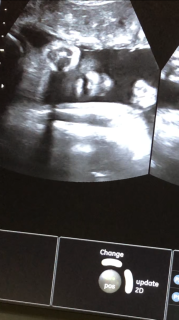

1377g! 前回よりも400g増えました! お口開けた瞬間!可愛い(^^)